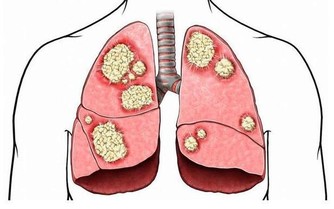

***4、戒菸酒,降低損傷***

吸煙,會加重胃炎、潰瘍病的病情,不利於胃炎、潰瘍病的康復。

據研究發現,吸煙者,潰瘍病的發病率,是非吸煙者的2-4倍。

每天吸煙20支以上的人,約40%可發生胃粘膜炎症。

酒精入胃,會直接損害胃粘膜,甚至引起炎症、癌變。

酒精度數越高,對於胃部的損害也就越嚴重,養護胃部要注意少碰酒飲。

所以,養護肺部健康,要戒菸忌酒。